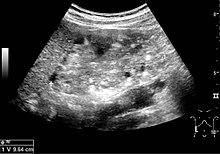

Angiomyolipoma seen as a hyperechoic mass in the upper pole of an adult kidney on renal ultrasonography.

Renal ultrasonography of a person with tuberous sclerosis and multiple angiomyolipomas in the kidney: Measurement of kidney length on the US image is illustrated by ‘+’ and a dashed line.